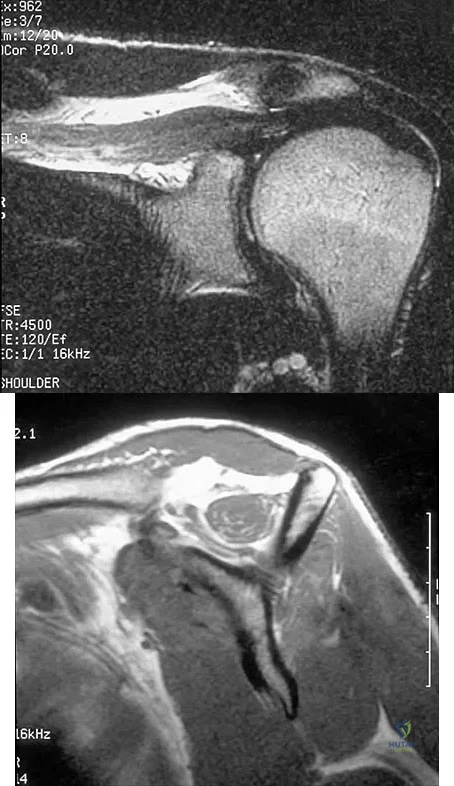

Figures 11a and 11b show the AP and lateral radiographs of a 32-year-old patient on hemodialysis who has increasing elbow pain and a visibly growing mass over the extensor surface. Figure 11c shows the photomicrograph of the biopsy specimen. What is the most likely diagnosis?

Figures 11a and 11b show the AP and lateral radiographs of a 32-year-old patient on hemodialysis who has increasing elbow pain and a visibly growing mass over the extensor surface. Figure 11c shows the photomicrograph of the biopsy specimen. What is the most likely diagnosis?

Explanation